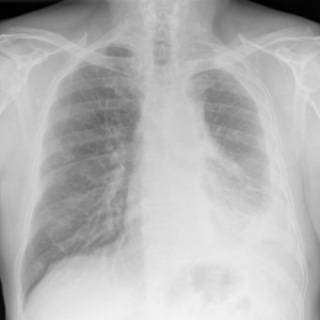

What Does Mesothelioma Look Like on an X-Ray?

Lighter and hazy areas on the X-ray show possible mesothelioma tumors.

On a chest X-ray, pleural or pericardial mesothelioma tumors appear as wispy white areas around the lungs, while calcified tumors appear bright white. Bones appear white and healthy lungs are dark. Most abnormalities appear as lighter areas that are hazy or solid.

Large fluid buildup called pleural effusions, a common mesothelioma symptom, can make an entire lung field look “cloudy” or even completely white on an X-ray. Tumors and scarring may distort chest anatomy. Compressed lungs or a raised diaphragm can be visible on an X-ray.

X-rays are 2D, making it hard to determine if a tumor is in the lung, pleura or the mediastinum around the heart. Additionally, X-rays don’t clearly show peritoneal or testicular mesothelioma. CT, MRI and PET/CT scans offer more detailed images for all mesothelioma types.